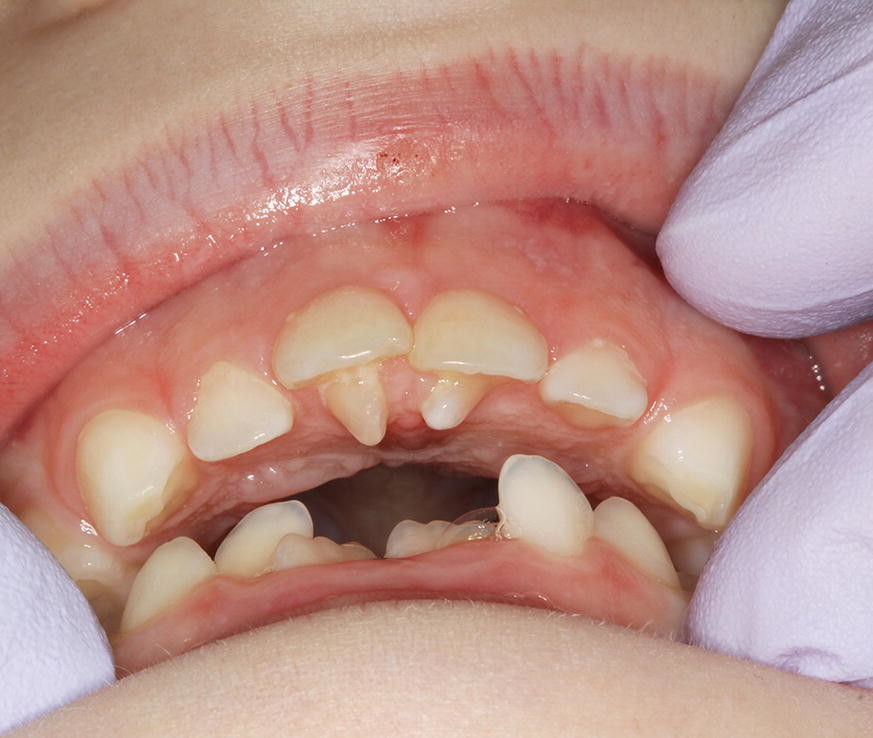

Impacted canines (49%)

Supernumeraries (16%)

Impacted second premolars (10%).

In addition to the service analysis described in part 1 of the BDJ series, in part 2 the authors provide an overview of common dental anomalies. Their definition, classification, aetiology and prevalence have been outlined along with their diagnosis and management. The aim of this is to increase awareness amongst practitioner's and help them formulate appropriate treatment plans. Part 1 of the series covers soft tissue anomalies, dentigerous cysts, transpositions and supernumerary teeth. Whereas part 2 focuses on impacted teeth, delayed and failed eruption, ankylosed incisors and infra-occluded deciduous molars.

The average age of patients presenting to the clinic with impacted canines was 17 years, this is a late presentation age. Impacted canines are a common dental anomaly and although there are a number of reasons for late referral, this service evaluation has highlighted an area where knowledge improvement may be beneficial. The age of presentation for unerupted central incisors was also late. We hope that the information presented in this two part series is useful for the whole dental team.